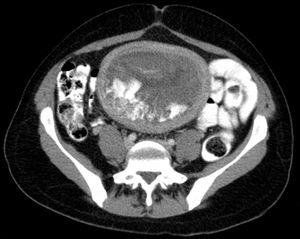

Hydatidiform mole on CT, sagittal view

Hydatidiform mole on CT, axial view